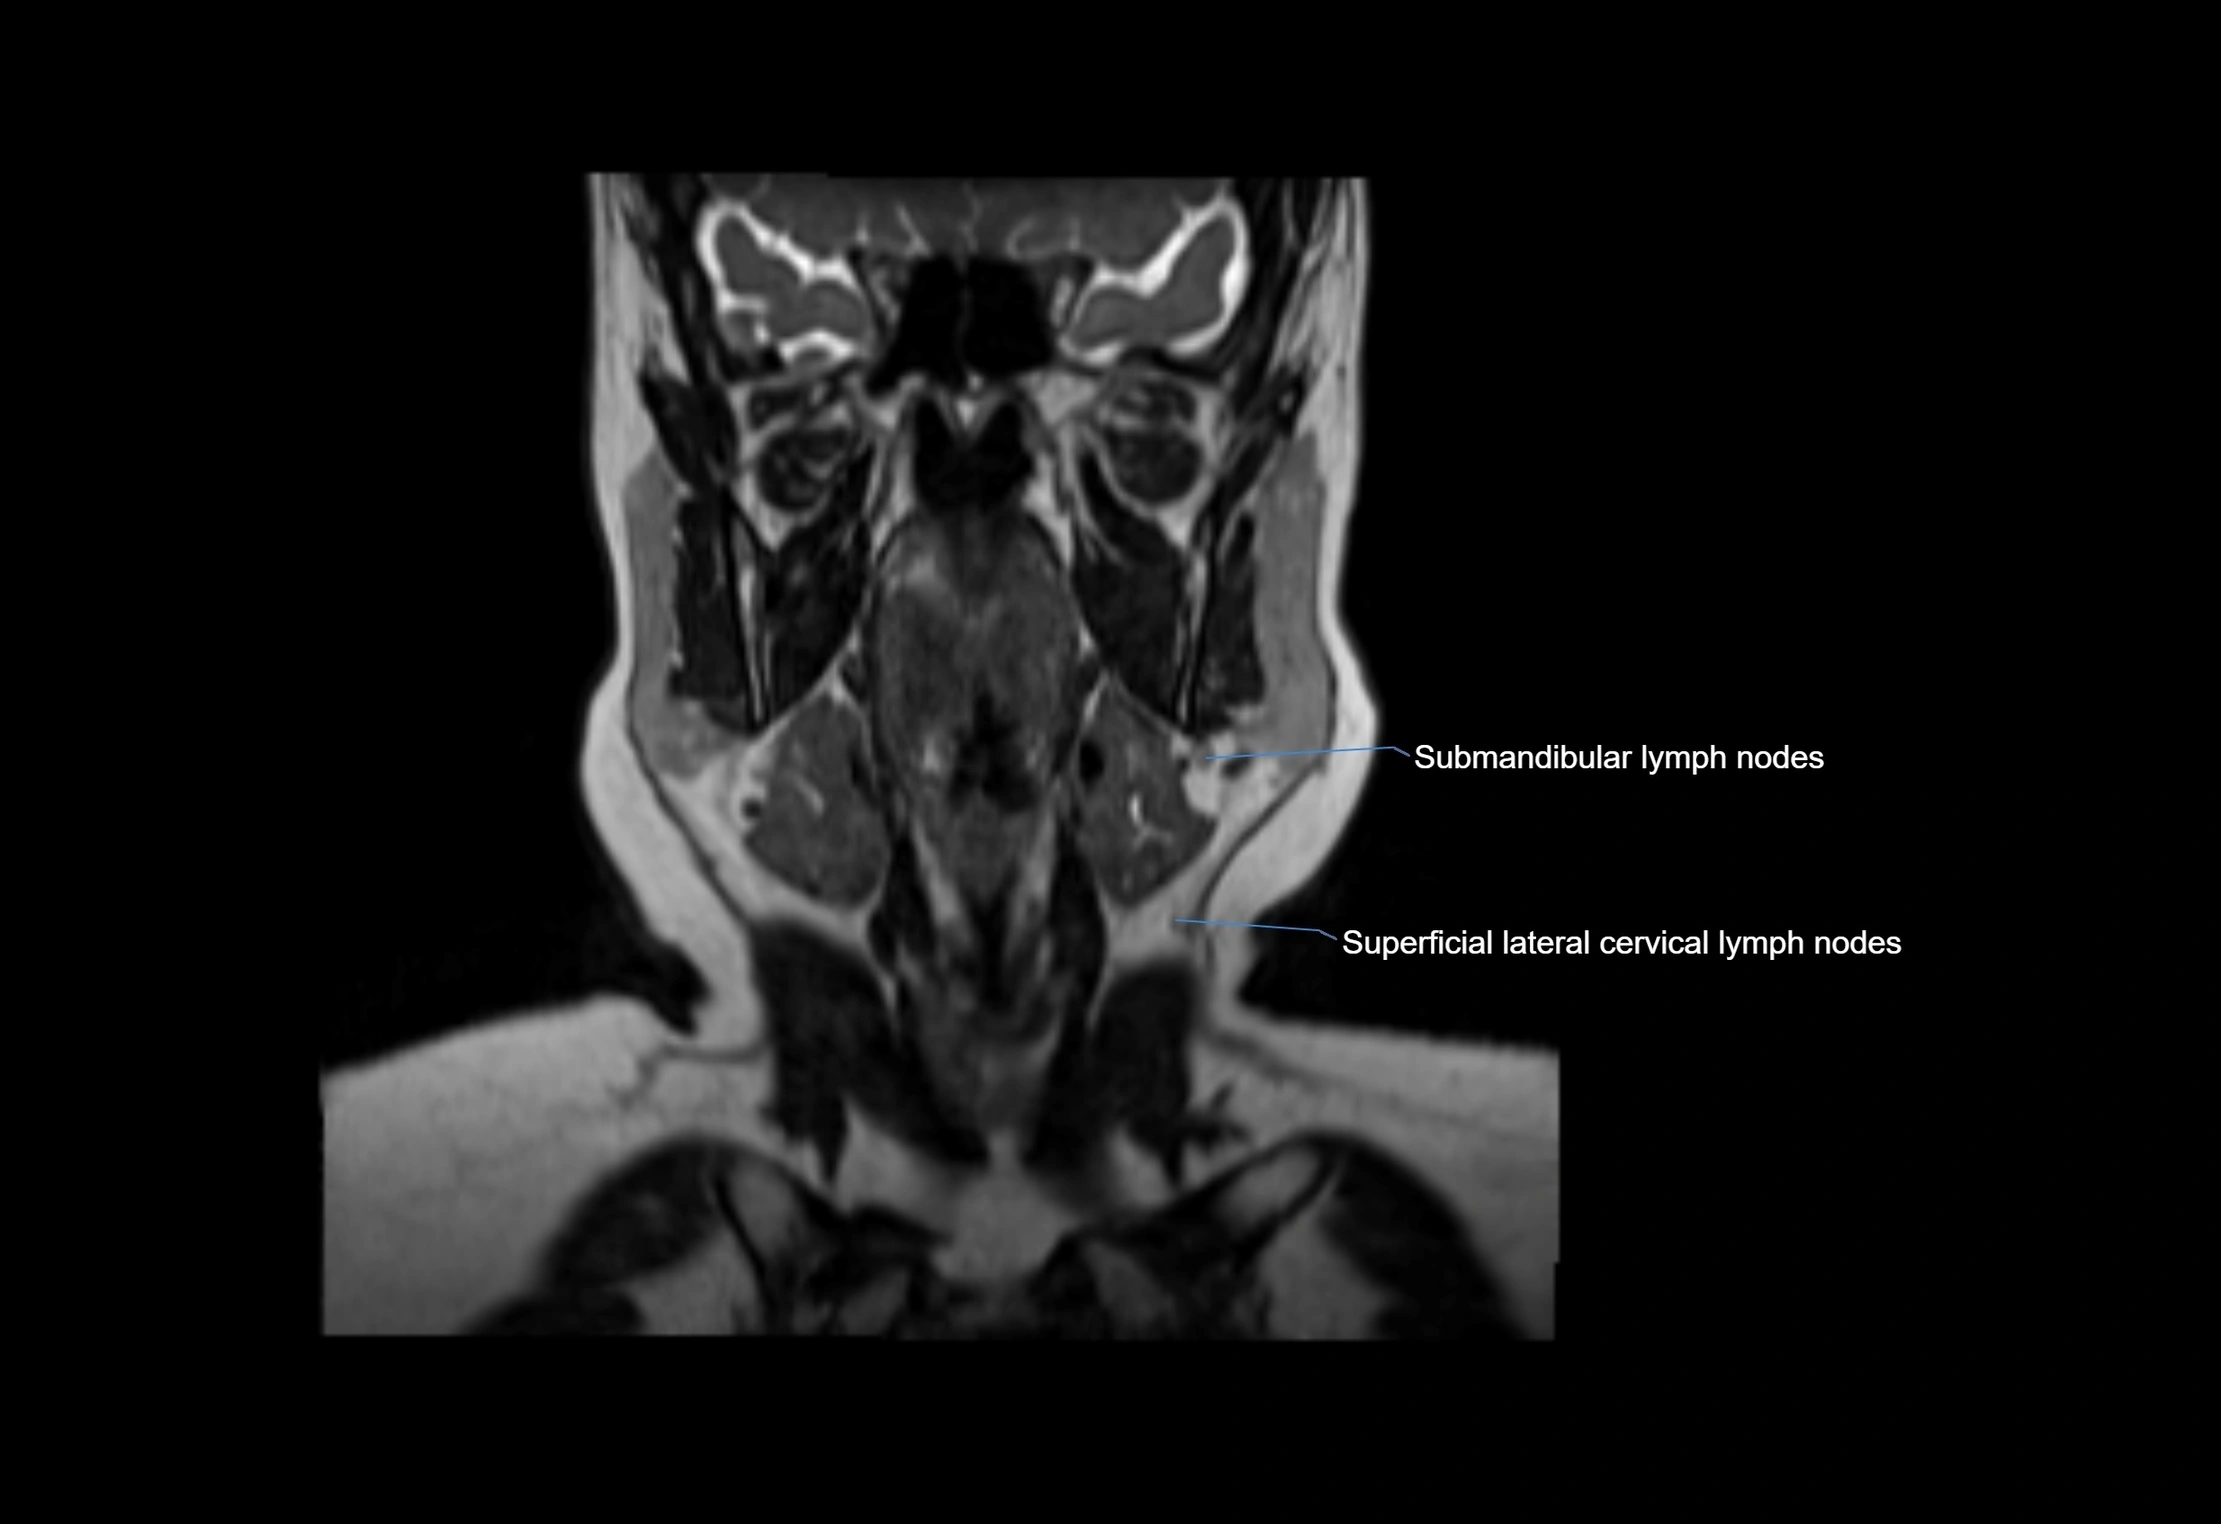

Location

• Found along primary lymph node chains, including preauricular, submandibular, parotid, and occipital regions

• Embedded in subcutaneous fat or superficial fascia, often lateral or posterior to primary nodes

MRI Appearance

T1-weighted images:

• Normal accessory nodes appear as small, oval hypointense to intermediate signal structures within subcutaneous fat

• Surrounded by hyperintense fat, enhancing contrast for visualization

• Pathological nodes may appear enlarged or rounded, sometimes with cortical thickening

T2-weighted images:

• Nodes show intermediate signal, with surrounding fat bright

• Useful for detecting edema, inflammation, or infiltration

• Fatty hilum may appear slightly hyperintense relative to cortex

MRI images

image